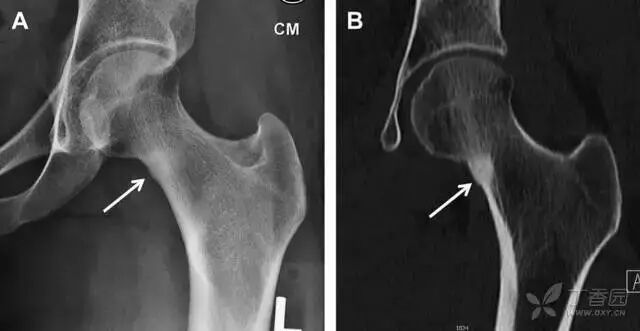

非典型股骨骨折

另一种易漏诊的骨折是非典型股骨骨折,这种骨折与长期服用双膦酸盐相关,常发生在使用双膦酸盐 3 年以上的患者。前驱症状表现为腹股沟痛或大腿痛的患者中,60%~70% 被错误地认为由腰背痛或髋关节炎引起。

这种骨折的一个典型表现为火山口状骨膜隆起及一横行透亮带。值得注意的是,超过 50% 的患者表现为股骨干完全骨折。由于 50%~60% 的患者会累及双侧,所以一旦一侧下肢确诊,需行对侧下肢检查。

图 10 老年患者长期服用双磷酸盐引起的骨折。A 髋部正位片,箭头所示,股骨外侧皮质存在横行透亮带。B 后续的股骨 X 线片示局灶性骨膜反应,以及此类骨折的特征性表现-火山口状骨膜隆起(箭头)。C MRI 冠状位 STIR 序列扫描示相应骨折平面的骨髓水肿表现